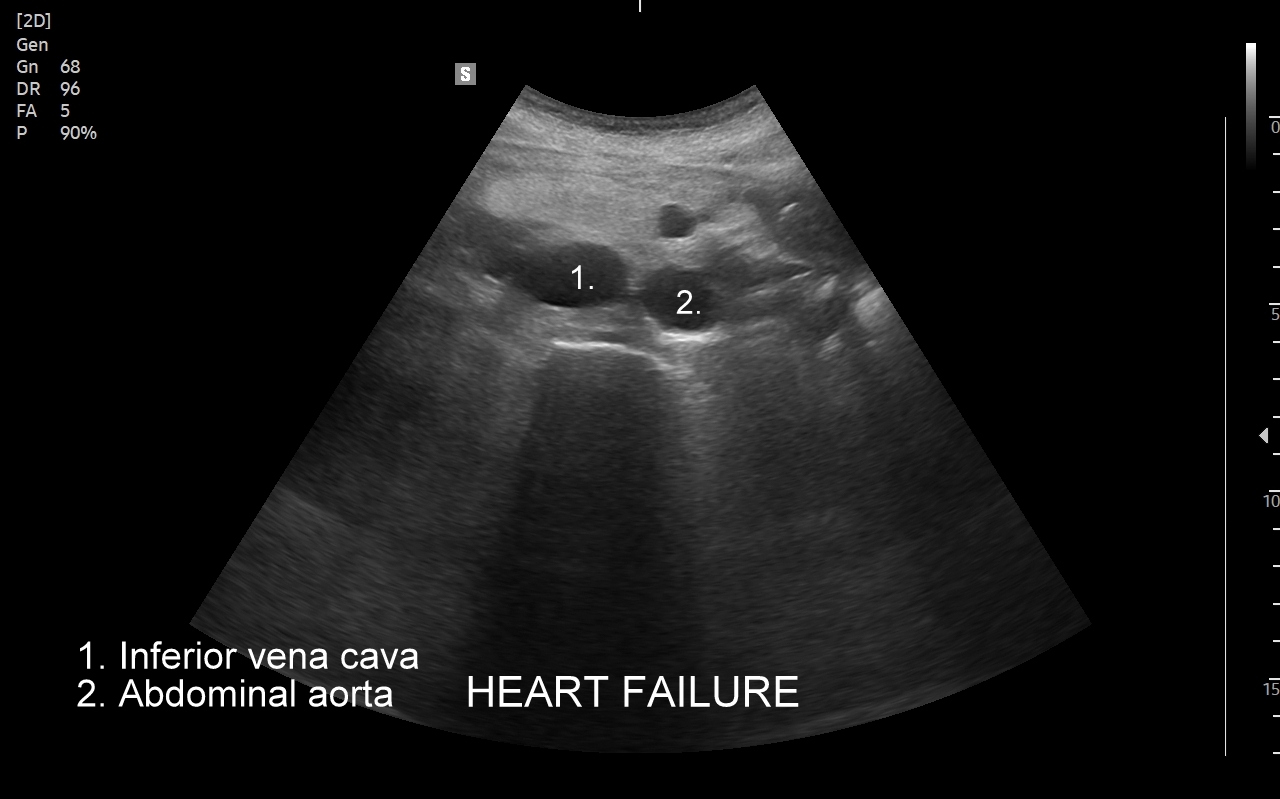

Badanie echokardiograficzne, nazywane także echo serca lub USG serca jest jedną z podstawowych metod diagnostyki kardiologicznej. W badaniu tym ocenia się zarówno morfologię narządu, jak i jego funkcję w postaci pomiarów wielkości jam serca, grubości mięśnia sercowego, czynności skurczowej oraz rozkurczowej lewej i prawej komory, oceny funkcji zastawek serca, wyglądu wsierdzia, osierdzia, a także w postaci pomiarów aorty, poszukiwania obecności patologicznych objawów sercowych związanych z chorobami innych narządów (np. choroby płuc, nadciśnienie tętnicze).

Wskazania do badania USG serca są bardzo szerokie i obejmują diagnostykę bólów w klatce piersiowej, przyczyn zmniejszonej tolerancji wysiłku, przewlekłego zmęczenia, duszności, obrzęków kończyn dolnych i wodobrzusza, ocenę powikłań nadciśnienia tętniczego i zawału serca, diagnostykę zaburzeń rytmu serca, zatorów tętniczych, udaru mózgu, diagnostykę przewlekłego kaszlu, utraty masy ciała, gorączki i powikłań anginy gardła w obrębie zastawek serca.